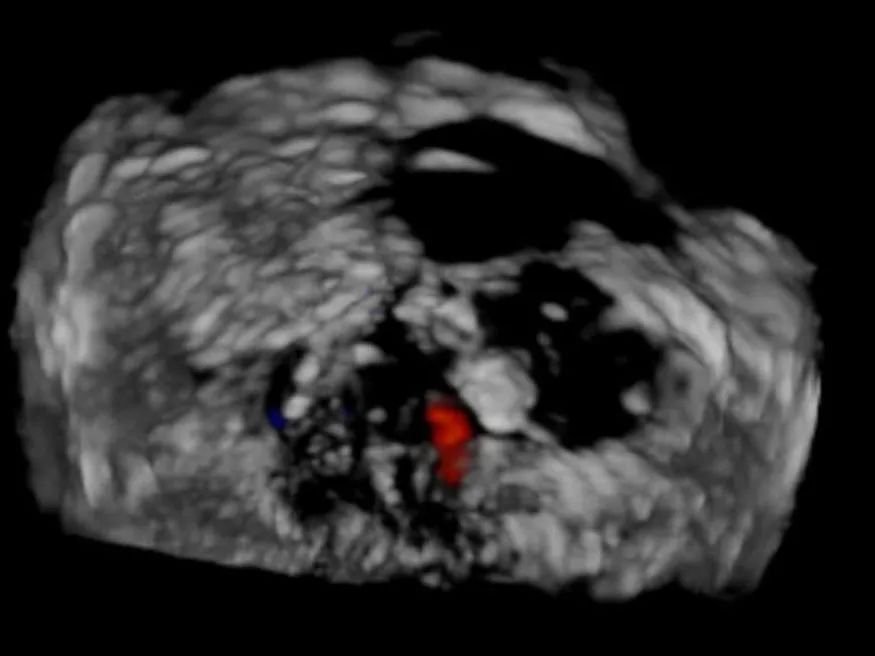

术后TEE(≤1+)

手术过程:手术采用经右侧股静脉入路,在TEE和DSA引导下完成房间隔穿刺,位置偏后偏上,穿刺高度为3.9厘米。置入瓣膜夹系统后,在左房调整瓣膜夹的轴向(orientation)和前进轨迹(trajectory),后进入左室进行瓣叶抓捕。由于两个瓣叶无法对合,后瓣叶较短,在尝试同时抓捕几次后,决定使用单独抓捕功能。先抓捕前瓣叶,再抓捕后瓣叶,确认瓣叶插入长度足够,缓慢关闭瓣膜夹。即刻返流程度降至轻度,跨瓣平均压差为2mmHg,最终成功释放瓣膜夹。采用“8”字缝合法关闭股静脉入路。术后肺静脉逆流和左房压都明显好转,预示着良好的预后。手术共耗时2小时,术后患者无明显不适,安返CCU继续观察。